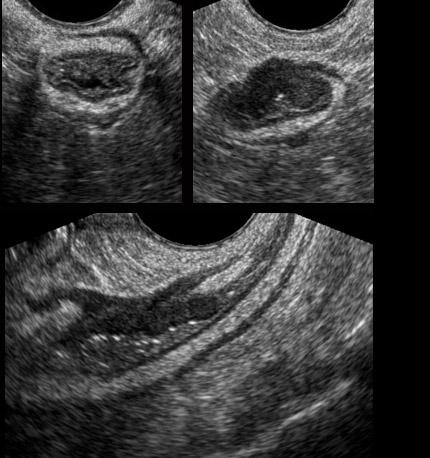

Hình ảnh giải phẫu TVUS của đại tràng sigma bình thường, có khả năng đè xẹp tốt, được khảo sát trên mặt cắt dọc và mặt cắt ngang.

Ở cuối chuỗi hình, trên mặt cắt ngang, đại tràng sigma dễ dàng bị đè xẹp bởi đầu dò (đầu mũi tên) áp vào xương cùng.

Viêm túi thừa

Bệnh nhân nữ, 34 tuổi, nhập viện vì đau cấp tính hố chậu trái.

TVUS ghi nhận thành đại tràng sigma dày khu trú và một túi thừa chứa sỏi phân (mũi tên), được bao quanh bởi lớp mỡ viêm (*), đại diện cho mạc treo và mạc nối, có tác dụng bao bọc ngăn chặn tình trạng thủng sắp xảy ra.

Ngày hôm sau, bệnh nhân cảm thấy tốt hơn nhiều và TVUS theo dõi cho thấy túi thừa rỗng, giảm âm, thành dày do phù nề (đầu mũi tên).

Sỏi phân dường như đã được tống xuất vào lòng đại tràng sigma.